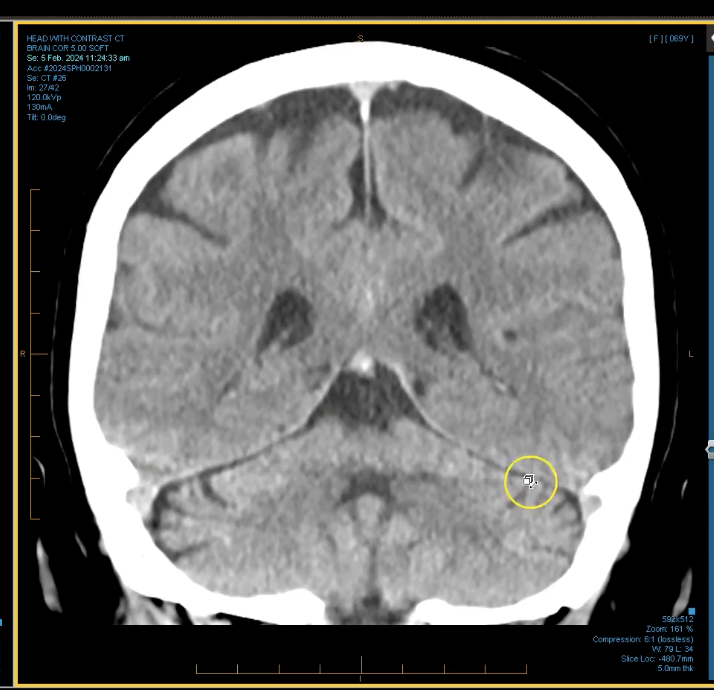

term image

thalamus